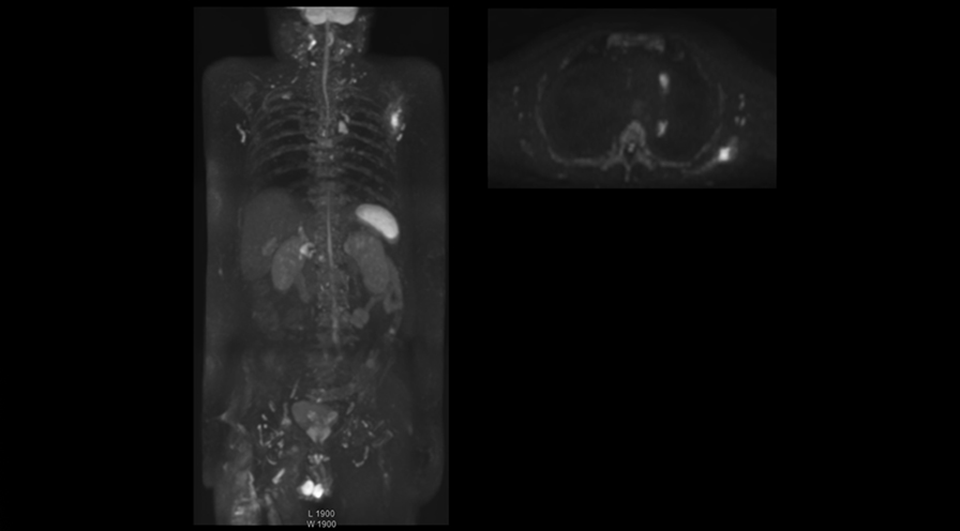

“Switching to coronal DWIBS – rather than axial – further shortens scan time,” says Mr. Naka. “Important is that a dS SENSE factor of 5 shortens exam time while high image quality can be maintained, thanks to Ingenia’s dStream architecture.” He adds that the coronal orientation also avoids artifacts that are specific to combining axial images.

“When we use a coronal DWIBS acquisition, we can perform a full whole body examination, including other required sequences, within 30 minutes,” he says.